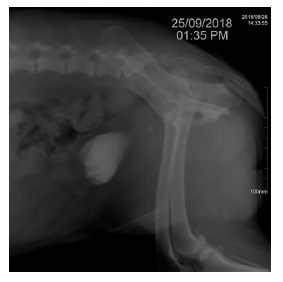

Se realiza ecografía focalizada para trauma abdominal (AFAST, por sus siglas en inglés) (Boysen y Lisciandro 2013) como prueba para el reconocimiento temprano de líquido libre en el abdomen, que en este caso arroja un resultado positivo para la presencia de líquido abdominal en las cuatro ventanas. Posteriormente, se realiza abdominocentesis con el paciente en decúbito lateral derecho para lavado y colecta de líquido peritoneal y se determina el valor de creatinina, cuyo resultado es de 8 mg/dl. Se lleva a cabo un lavado peritoneal con cloruro de sodio 0,9% con el fin de estabilizar al paciente y luego se procede a realizar una radiografía simple (figura 1), una uretrocistografía retrograda (figura 2) con medio de contraste positivo, en este caso iopramida (Ultravist®), en la cual se observa la disrupción uretral y zonas radiopacas en abdomen compatibles con la presencia de medio de contraste en el abdomen caudal, cuyo resultado es positivo para ruptura uretral. Se toman muestras de sangre para cuadro hemático y química sanguínea (ALT, creatinina, potasio, albúmina, calcio) en el que se observan como anormalidades el aumento de creatinina en valores de 2,5 mg/dL y anemia normocítica hipocrómica. No fueron autorizadas la totalidad de los exámenes solicitados. Se realiza un electrocardiograma en el cual no se encuentran anormalidades. Se sugiere la realización de laparotomía exploratoria para verificar daños adyacentes y ubicar y reparar el sitio exacto donde se produjo el rompimiento del tracto urinario inferior.

Fuente: elaboración propia.

FIGURA 1 Proyección latero-lateral izquierda/ derecha de abdomen. En la imagen se observa pérdida de la diferenciación del contorno de los órganos abdominales, densidad radiopaca compatible con líquido libre en el abdomen.